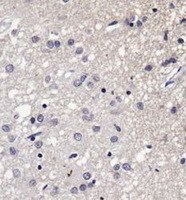

Supportive validation

- Submitted by

- OriGene (provider)

- Main image

- Experimental details

- Immunohistochemistry: SERF1A Antibody - IHC analysis of SERF1A in human Alzheimer's brain using DAB with hematoxylin counterstain.

- Validation comment

- IHC